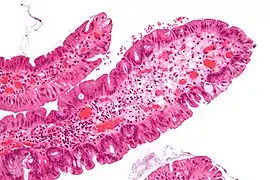

| Peutz-Jeghers Polyp | All digestive tract | Smooth muscle bundles between nonneoplastic epithelium, "Christmas tree" appearance | No |  |